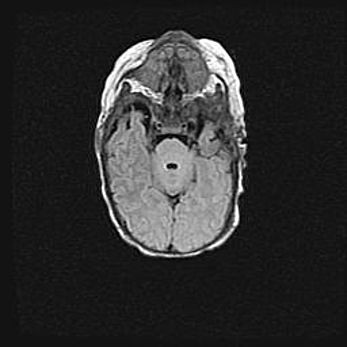

Сообщающаяся гидроцефалия. Кистозная энцефаломаляция головного мозга.

Возраст: 3 месяца 4 дня

Вес: 3100 г

Пол: женский

Окружность головы: 34 см

Срок гестации: 31 неделя

Кистозная энцефаломаляция головного мозга - одна из форм поражения головного мозга в детском возрасте. Характеризуется возникновением множественных и распространённых кист в коре, белом веществе и подкорковых образованиях головного мозга у плодов, новорождённых и детей раннего возраста. Развитие кистозной энцефаломаляции связано с внутриутробной асфиксией и гипотонией, родовой травмой, тромбозом синусов, пороками развития сосудов, инфекциями, сепсисом и другими причинами. Наиболее значимые инфекционные агенты: вирусы простого герпеса, цитомегалии, краснухи, токсоплазмы, энтеробактерии, золотистый стафилококк и другие.